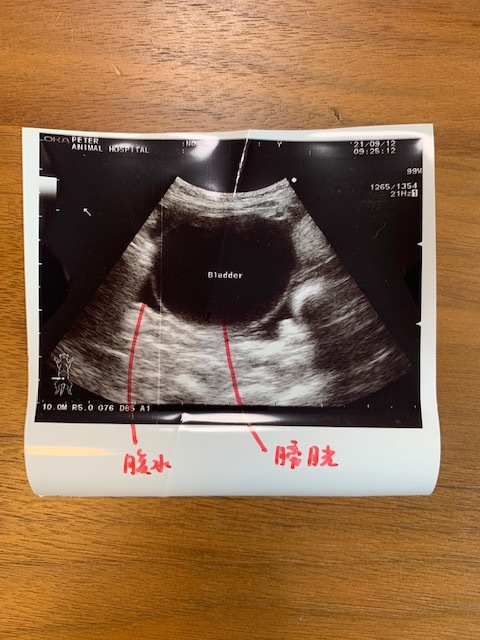

9月12日(日)午前

赤血球(PCV)濃度の低下(貧血)が進行、さらに腹水が溜まりはじめていることが判明し、

その時の担当医に、

「症状からして【FIP】という難病かもしれず、余命数日〜数週間です」と

突然、宣告されました。

(9月12日午前 急に溜まり始めた腹水)